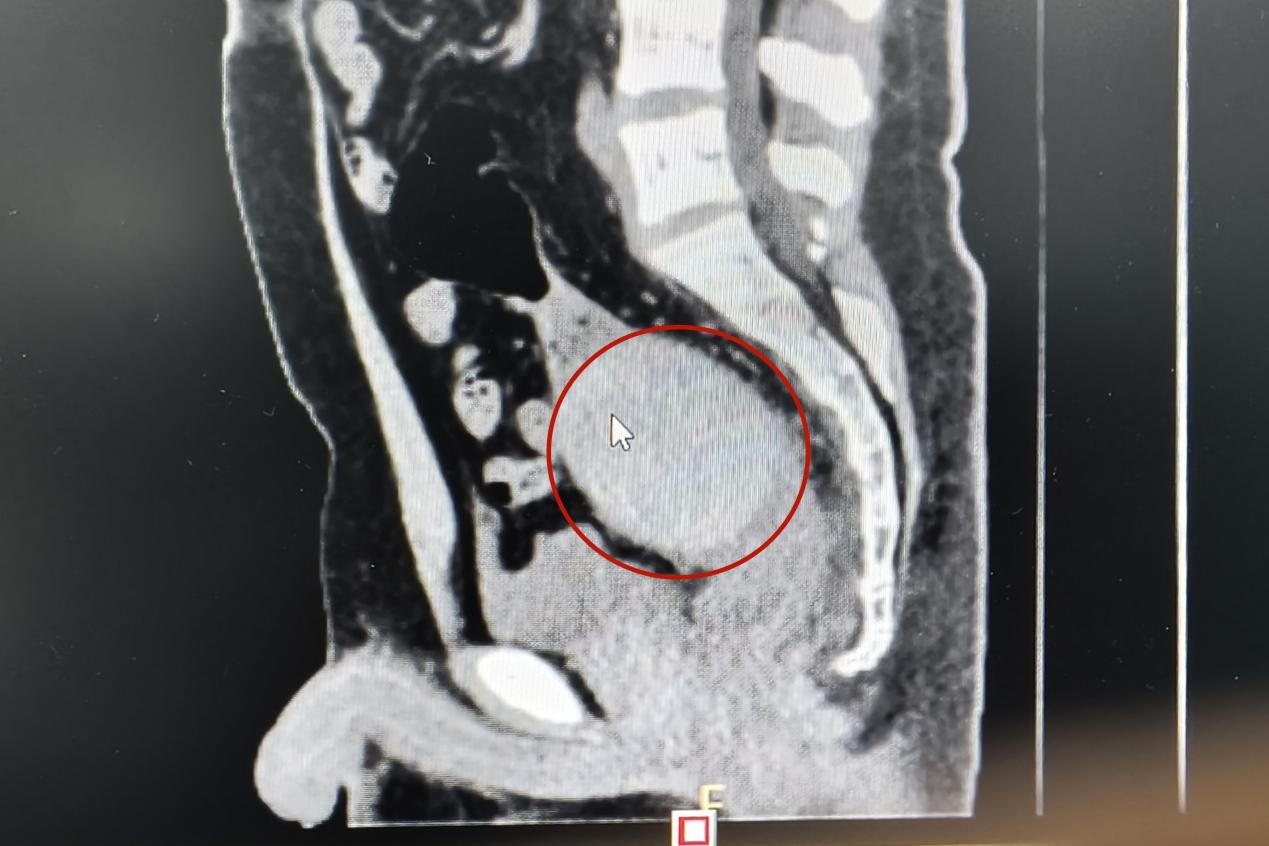

當(dāng)天下午,一名青年男子來(lái)到衡陽(yáng)市中心醫(yī)院肛腸外科門診就醫(yī),稱肛門內(nèi)有異物,肚子疼得很。李祥樂仔細(xì)詢問(wèn)病情,男子卻總是支支吾吾??此?/span>表情痛苦李祥樂便讓他躺到治療床上,對(duì)其進(jìn)行了肛門指檢。“你這個(gè)異物卡得很深,指檢觸不到,需要馬上做個(gè)CT明確位置?!崩钕闃芬贿吀嬷颊咭贿呍儐?wèn),“這個(gè)東西卡進(jìn)去多久了?”得知是昨晚發(fā)生的事,李祥樂心頭一驚,卻表面平和地安慰患者道:“沒事的,到醫(yī)院來(lái)你就放寬心了,等檢查結(jié)果出來(lái)我們想辦法給你取”。CT結(jié)果顯示患者異物位于直腸與乙狀結(jié)腸交界處,位置特殊,加之卡頓時(shí)間長(zhǎng),取的過(guò)程中腸道破裂出血的風(fēng)險(xiǎn)隨之增加。“我可以嘗試給你經(jīng)肛門取,但是如果取不出來(lái)那就需要進(jìn)行腹腔手術(shù)了”。